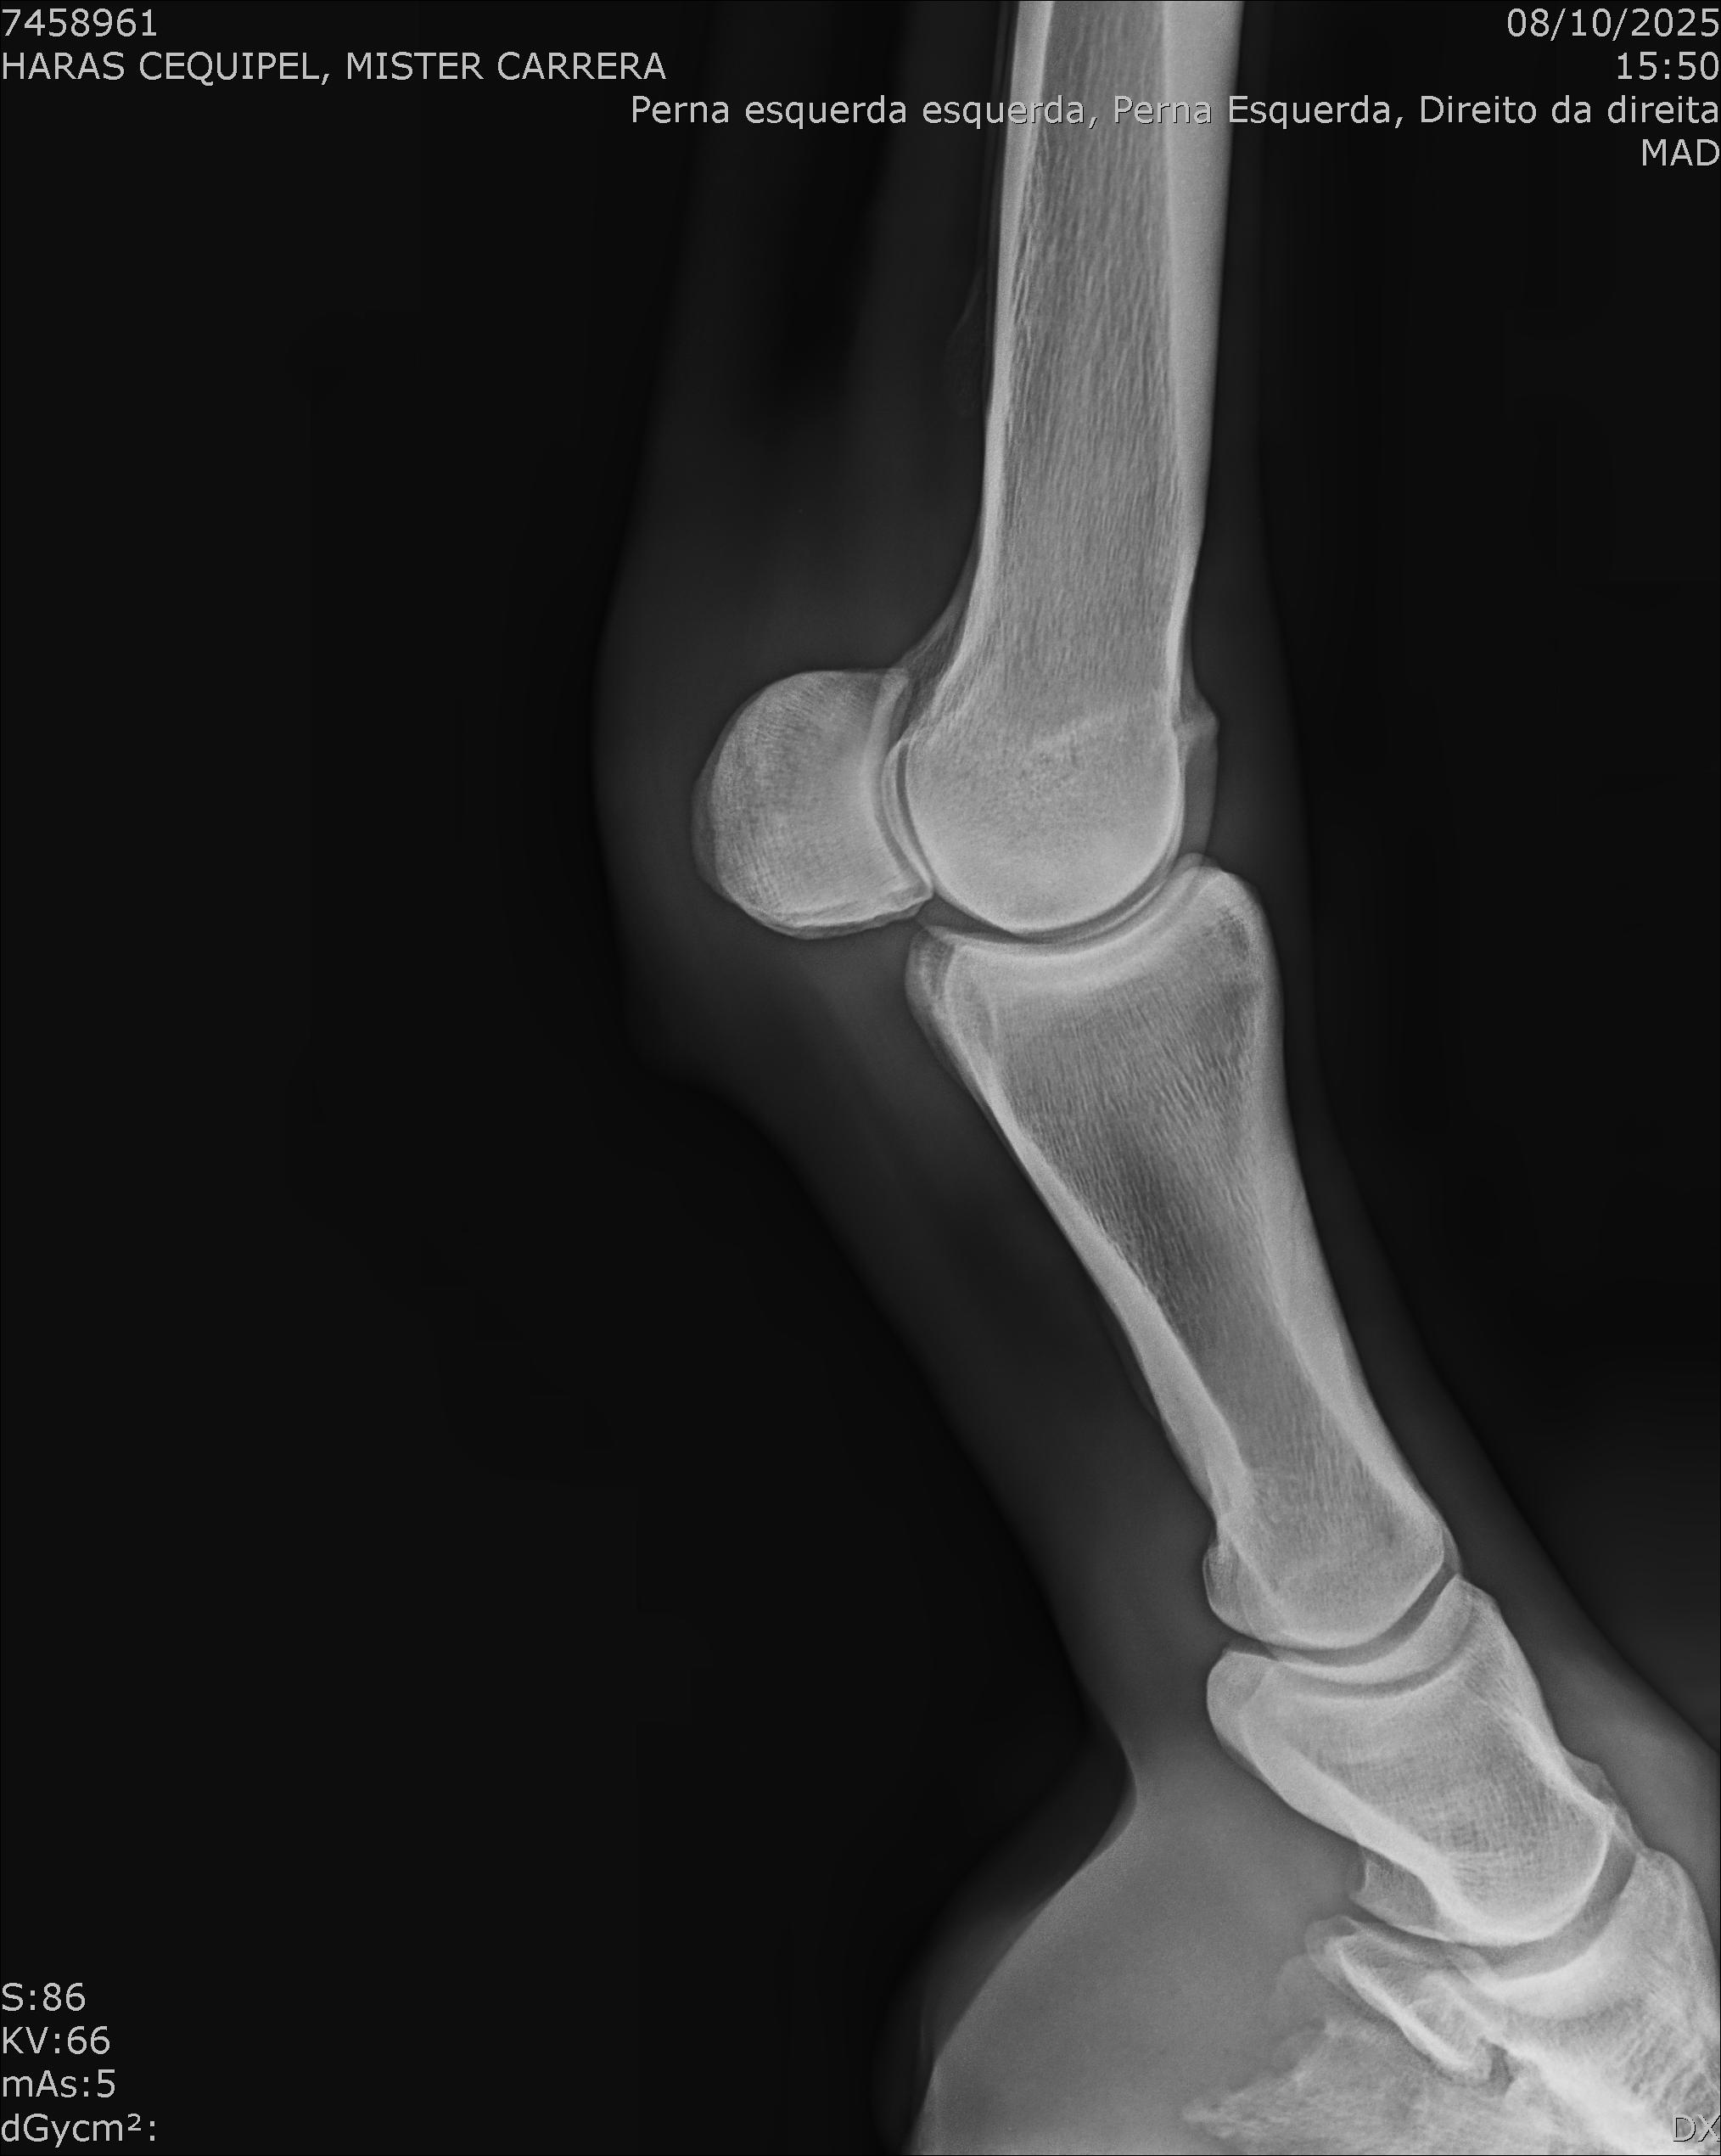

:: RAIOS-X DO LOTE